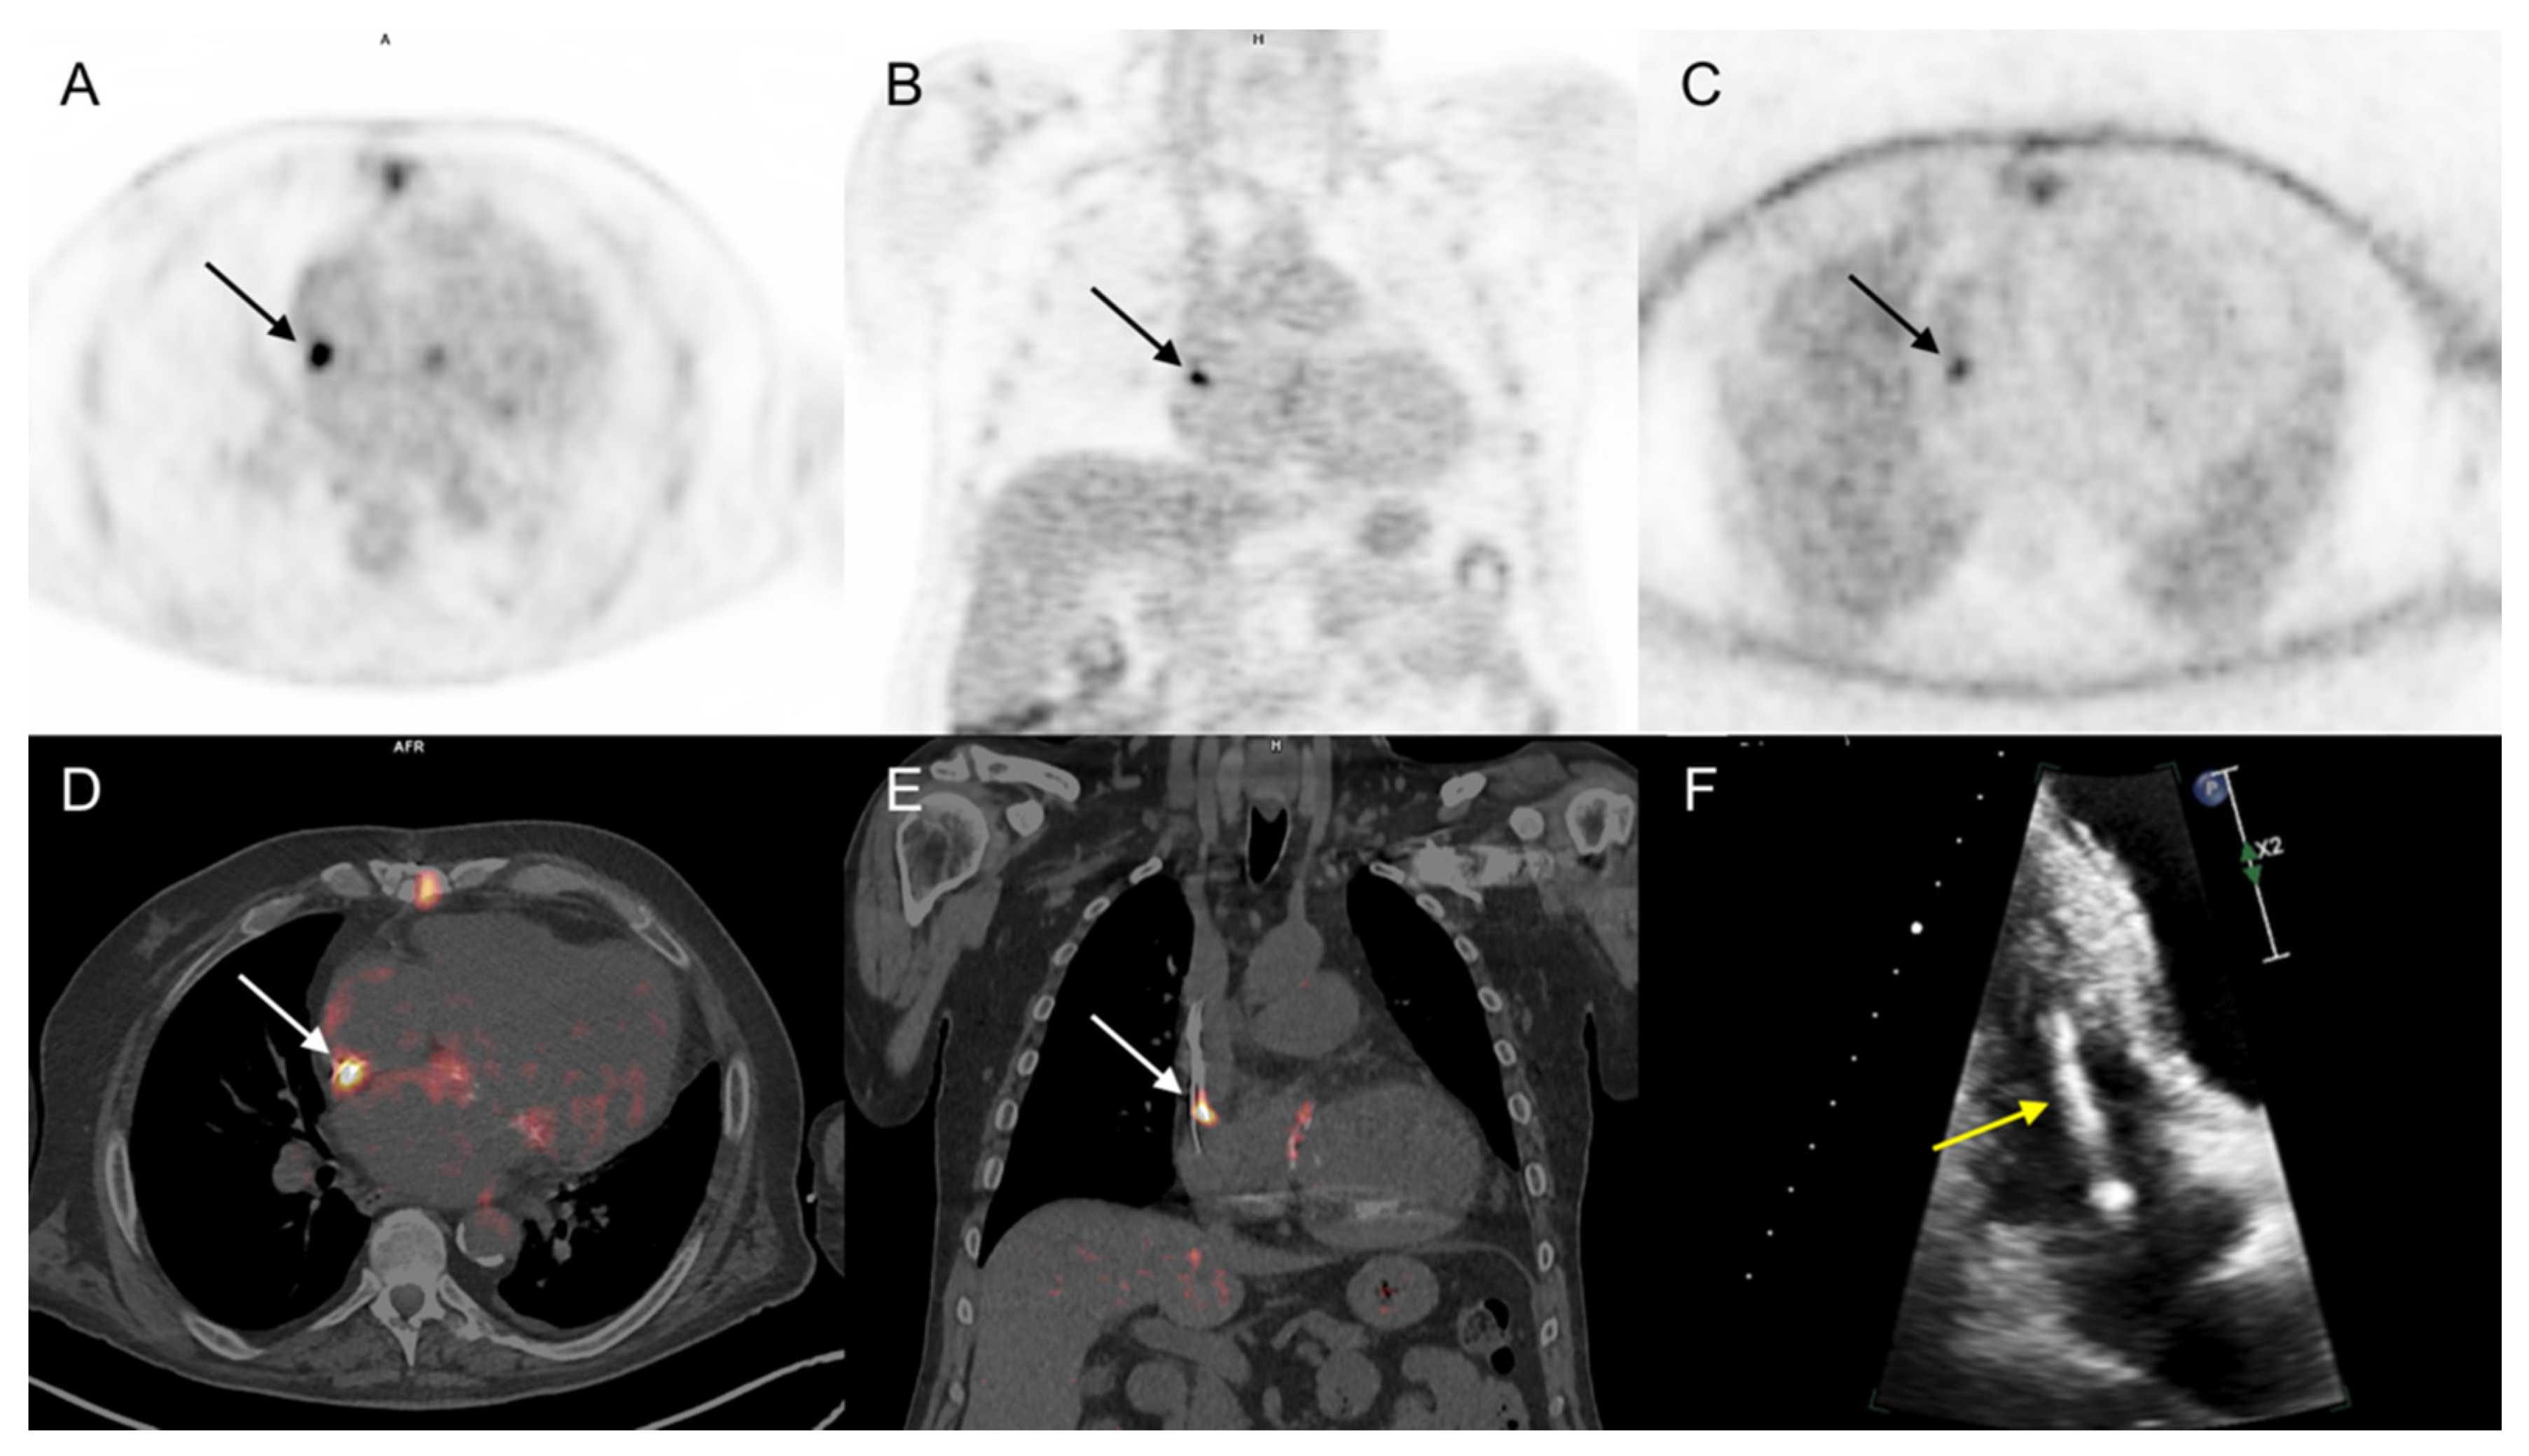

| 4, 48, F | Rej/High | IE | PM lead | - | - | - | Predisposition, fever |

| 5, 50, M | Rej/High | IE | LVAD | - | - | - | Fever, microbiologic evidence (Staphylococcus aureus) |